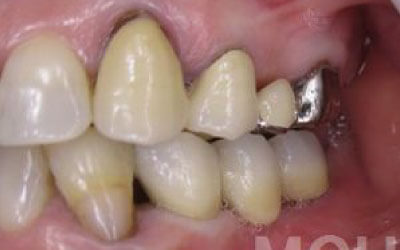

2 歯が傾いてくる、落ちてくる

歯はお互いに支え合ってバランスを取っています。ですので、歯が抜けるとその支えがなくなり、抜けた部分の隣の歯が倒れたり、上の歯が下に下がってくることがあります。